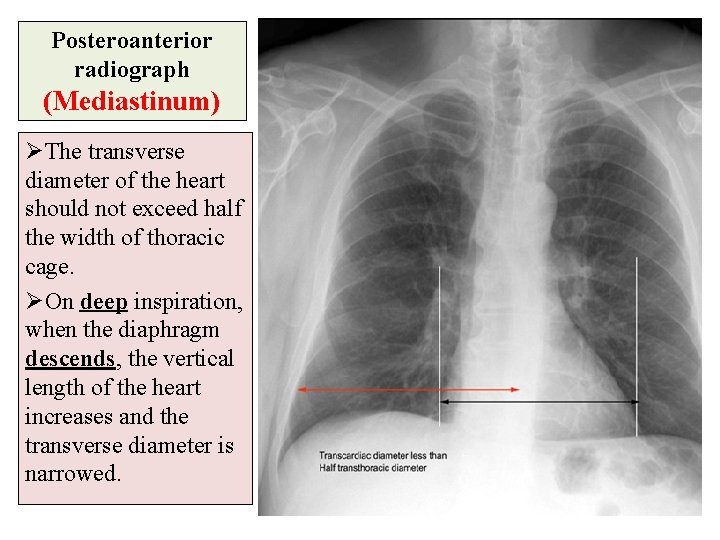

Posteroanterior radiograph (Mediastinum) ØThe transverse diameter of the heart should not exceed half the width of thoracic cage. ØOn deep inspiration, when the diaphragm descends, the vertical length of the heart increases and the transverse diameter is narrowed.